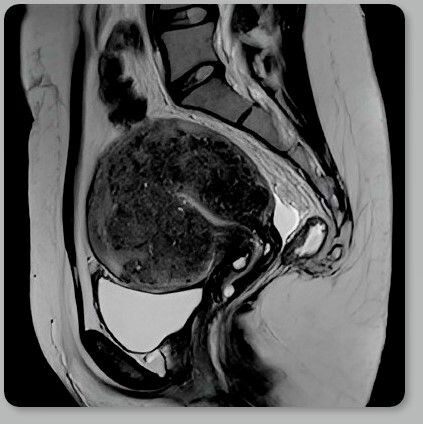

Вот так на МРТ выглядит матка с тяжелой степенью аденомиоза – она увеличилась в размерах и приобрела форму шара. Вместе с этим в области расположения самих очагов возникает местный отек и воспаление, что, с одной стороны, способствует возникновению болевого синдрома, а с другой, благодаря действию местного иммунитета, приводит к фиброзу и формированию аденомиом – это узловая форма аденомиоза. Не путать с миомой матки, это совершенно разные заболевания.